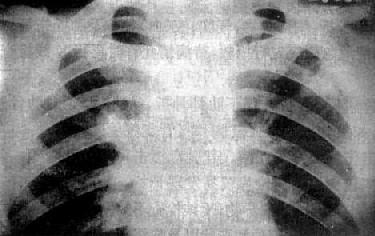

粟粒型肺结核病灶小,透视常难以辩认,故拟诊急性粟型肺结核时应摄片检查。病变早期整个肺野可呈毛玻璃样密度增高。约10日后可出现均匀分布的1.5~2mm大小、密度相同的粟粒状病灶,正常肺纹理常不能显示(图3-1-22)。经过适当治疗后。病灶可在数月内逐渐吸收,偶尔以纤维硬结或钙化而愈合。病变恶化时,可以发生病灶融合,表现为病灶增大,边缘模糊,甚至形成小片状或大片状影,并可干酪样化而形成空洞。

急性粟粒型肺结核

图3-1-22 急性粟粒型肺结核

两肺野布满粟粒状病灶,分布均匀,肺门大